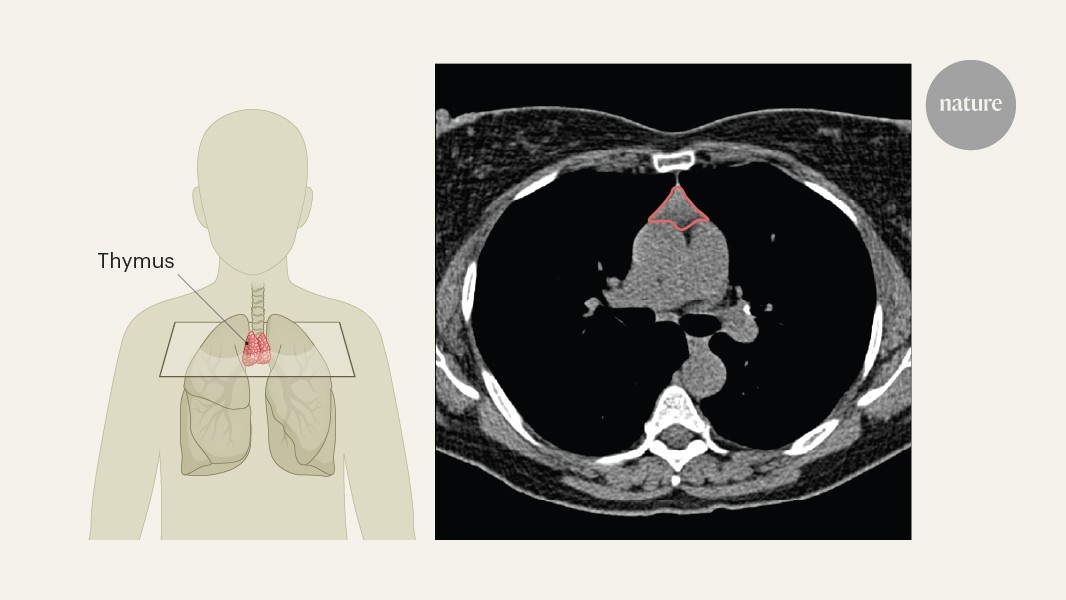

Golzari-Sorkheh, M., Yoganathan, K., Chen, E. L. Y., Singh, J. & Zúñiga-Pflücker, J. C. in Thymus Transcriptome…